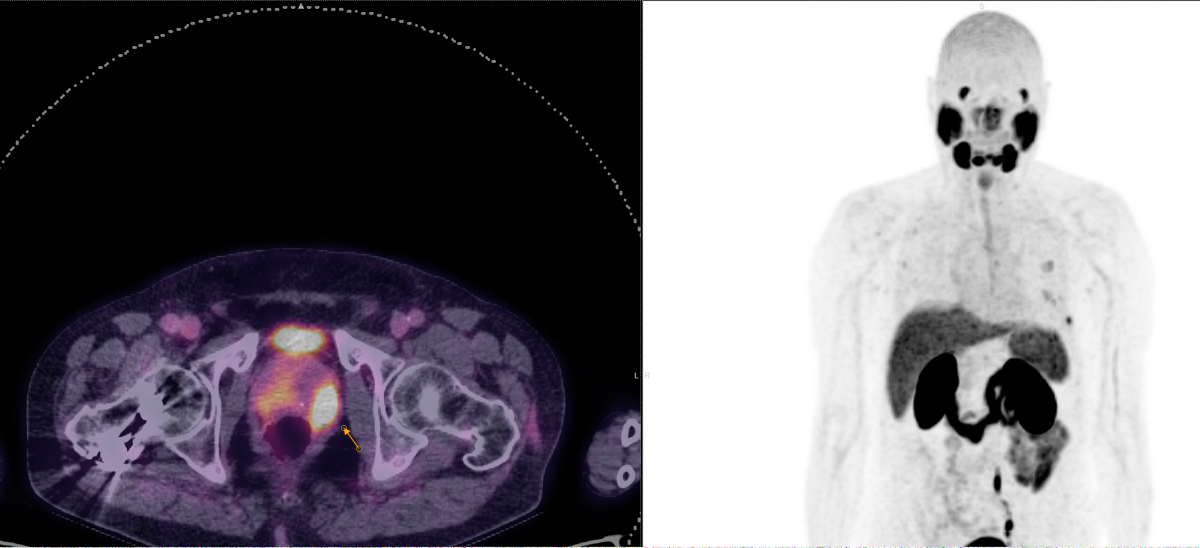

Η Τομογραφία Εκπομπής Ποζιτρονίων (PET) αποτελεί μια εξειδικευμένη μέθοδο της Πυρηνικής Ιατρικής που χρησιμοποιεί μοριακή απεικόνιση για να εντοπίσει και να παρακολουθήσει φυσιολογικές και παθολογικές λειτουργίες του οργανισμού. Συνδυάζοντας τη λειτουργική απεικόνιση της PET με την ανατομική πληροφορία της αξονικής τομογραφίας (CT), η υβριδική εξέταση PET/CT παρέχει εικόνες υψηλής ευκρίνειας και τη δυνατότητα ποσοτικής αξιολόγησης των βιολογικών μηχανισμών σε κυτταρικό επίπεδο.

Η PET/CT αποτελεί εξαιρετικά προηγμένη τεχνική της σύγχρονης ιατρικής απεικόνισης και χρησιμοποιείται τόσο για τη διάγνωση όσο και για την παρακολούθηση της ανταπόκρισης στη θεραπεία.

Στην ογκολογία, η PET/CT συμβάλλει με εξαιρετική ακρίβεια:

Η εξέταση είναι ανώδυνη και ασφαλής, πραγματοποιείται μετά από ενδοφλέβια χορήγηση ραδιοφαρμάκου (συνήθως ¹⁸F-FDG) και καλύπτει συνήθως ολόκληρο το σώμα – από την κορυφή της κεφαλής έως τα πέλματα.

Στο Κέντρο PET/CT πραγματοποιούνται εξειδικευμένες εξετάσεις που καλύπτουν ένα ευρύ φάσμα κλινικών εφαρμογών στη σύγχρονη Πυρηνική Ιατρική. Ανάλογα με το είδος του προβλήματος και τη φύση της νόσου, χρησιμοποιούνται διαφορετικά ραδιοφάρμακα για τη μελέτη συγκεκριμένων βιολογικών μηχανισμών.

PSMA‑θετικός καρκίνος προστάτη